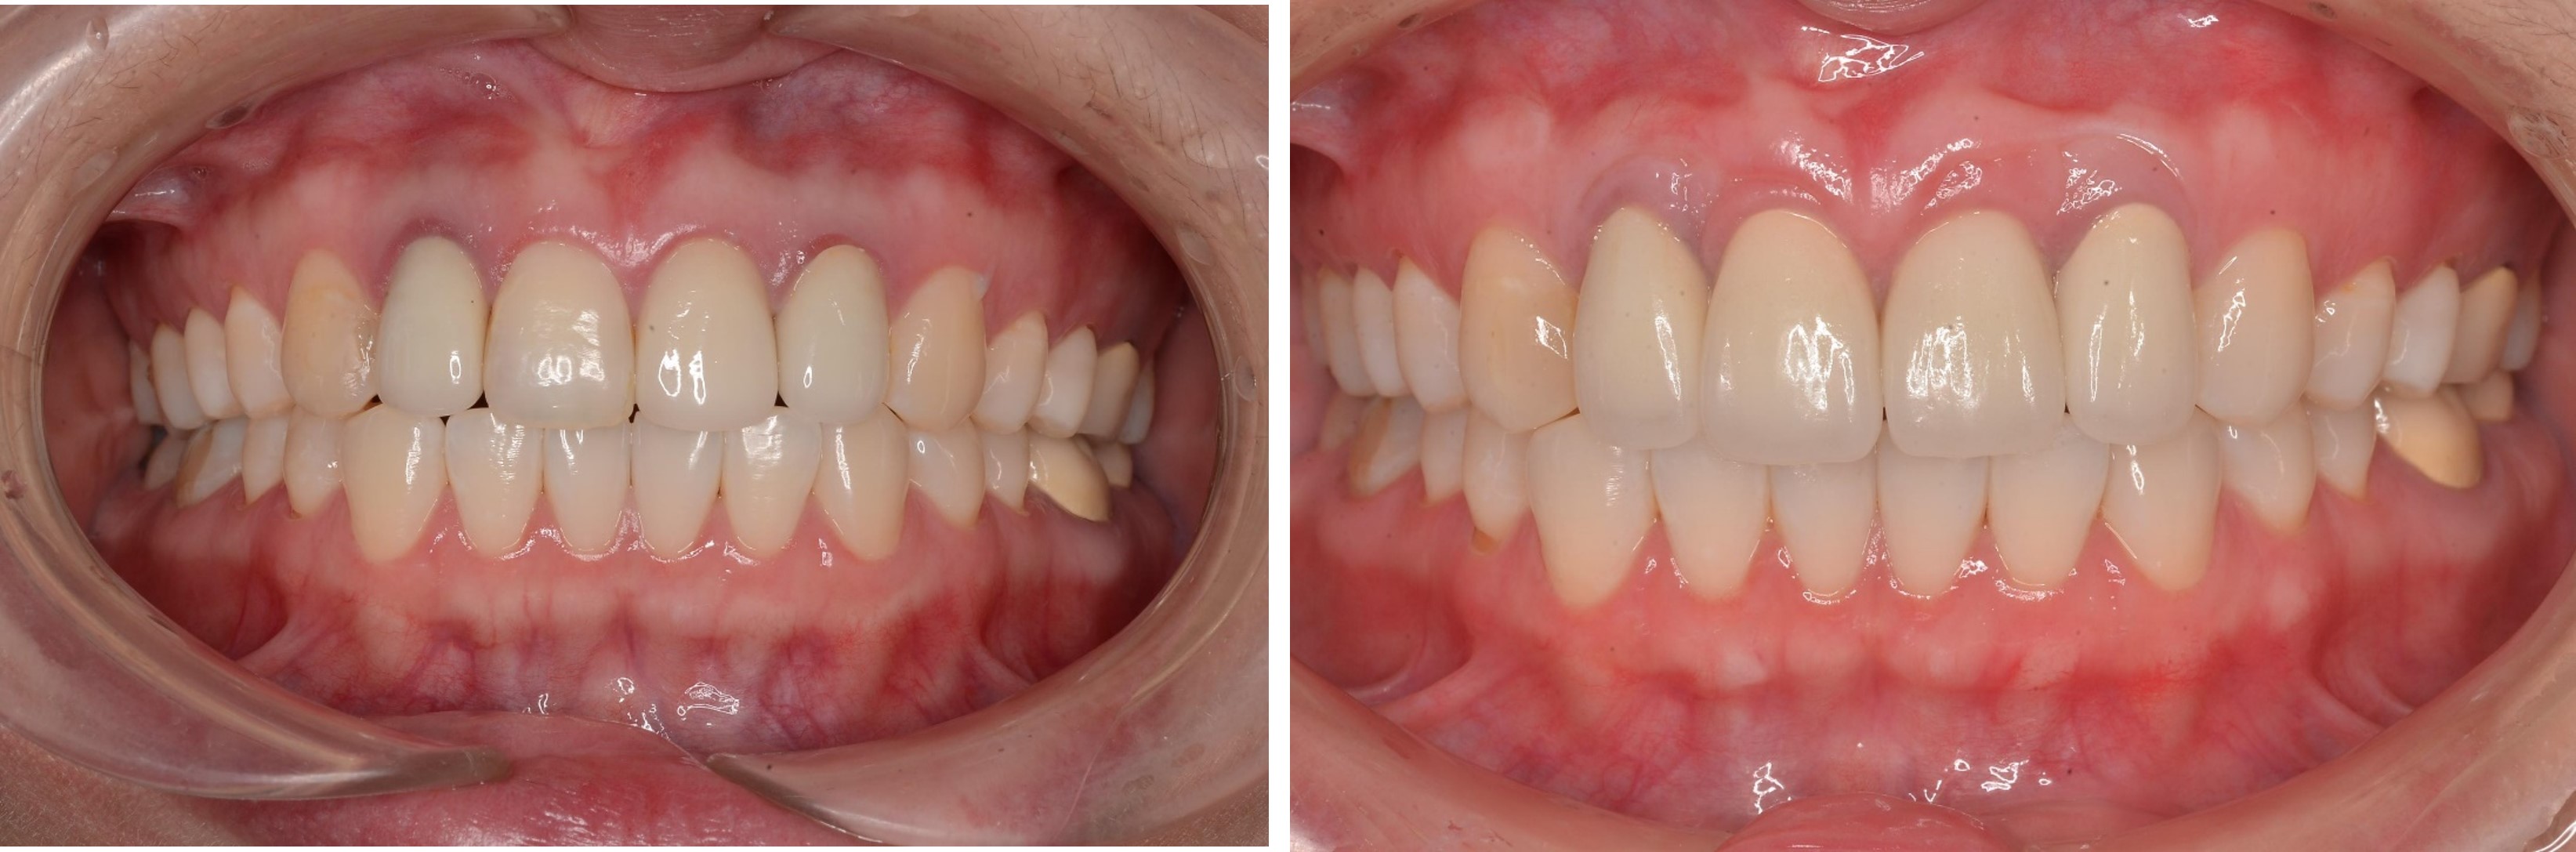

術前、術後比較

治療前,牙齦旁有黑邊

治療前,微笑時上牙不易容露出

前牙美觀與功能兼顧

微笑時,患者開心